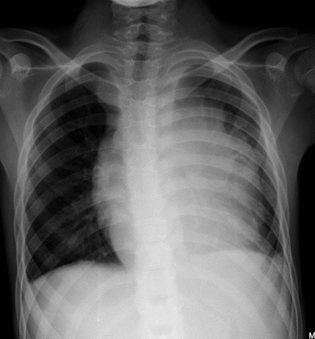

- Linfoma de Hodgkin (LH): O quadro clássico é uma massa tumoral de crescimento progressivo e contíguo, 60% em região cervical ou supraclavicular. 2/3 dos pacientes apresentam alargamento do mediastino. A presença de Sintomas B (febre, perda de peso > 10% em 6 meses, sudorese noturna) é fundamental.

- Diagnóstico: RX ósseo com imagem característica de “raios de sol” (sunburst). O principal sítio de metástase é o pulmão.